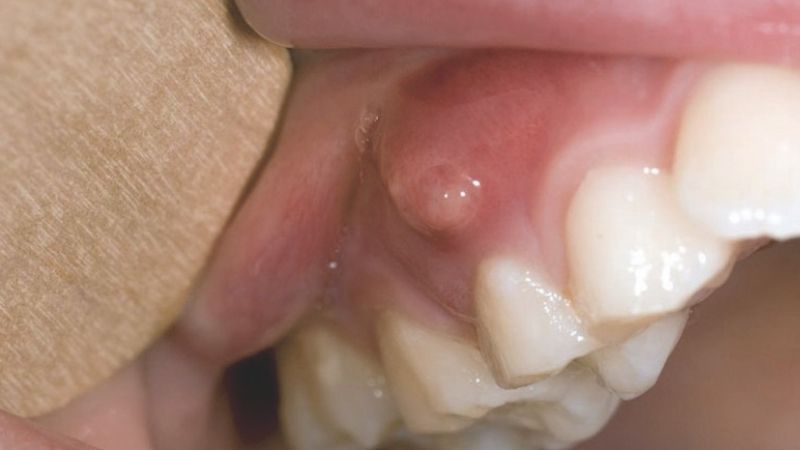

Áp xe răng là tình trạng nhiễm trùng cấp tính xảy ra tại vị trí quanh chân răng hoặc mô nướu, tạo thành túi mủ chứa vi khuẩn, mảnh vụn tế bào và dịch viêm. Ở trẻ em, áp xe răng thường xuất hiện do viêm tủy răng hoặc sâu răng không được điều trị đúng cách, dẫn đến vi khuẩn xâm nhập sâu vào bên trong cấu trúc. Áp xe răng ở trẻ em không chỉ gây đau đớn, khó chịu mà còn ảnh hưởng đến khả năng ăn uống, phát âm và sự phát triển của hàm răng vĩnh viễn sau này nếu không được xử lý kịp thời.

2. Sưng tấy vùng má hoặc nướu

Khu vực quanh răng bị áp xe thường sưng đỏ, có thể nhìn thấy một hoặc nhiều ổ mủ nhỏ màu trắng hoặc vàng.

1. Rạch dẫn lưu mủ

Bác sĩ sẽ tiến hành rạch một đường nhỏ để thoát mủ, giảm áp lực và giảm đau cho trẻ.